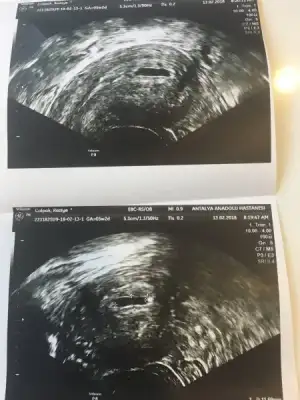

5.haftada kesesi vajinal yoldan gördü doktor henüz içinde bebeği göremedik ama yolksac oluşuyor dedi onu gördü.

internette biryerde rast geldim kesenin şekli kalemle çizilmiş gibi yuvarlar olmalıymış eger girinti çıkıntı varssa kese basıncı ve sıvısı yetersiz olabiliyormuş. benim kesemde de var sanki girinti çıkıntı sizce böyle şeyler normal mi sorun yaşayabilir miyim. bilen varmı bı yorum yapsanız

• ultrason.webp

ultrason.webp

24,3 KB · Görüntüleme: 77